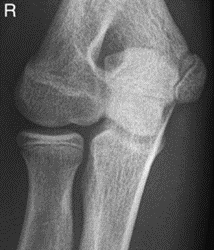

Świadczenie usług medycznych …

W ułożeniu do rentgenografii AP stawu kolanowego promień główny pada

A. prostopadle na podstawę rzepki.

B. pod kątem 30° na podstawę rzepki.

C. pod kątem 30° na wierzchołek rzepki.

D. prostopadle na wierzchołek rzepki.